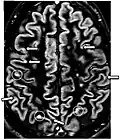

| Double inversion recovery | DIR | Simultaneous suppression of cerebrospinal fluid and white matter by two inversion times.[16] | High signal of multiple sclerosis plaques (pictured).[16] |

| |